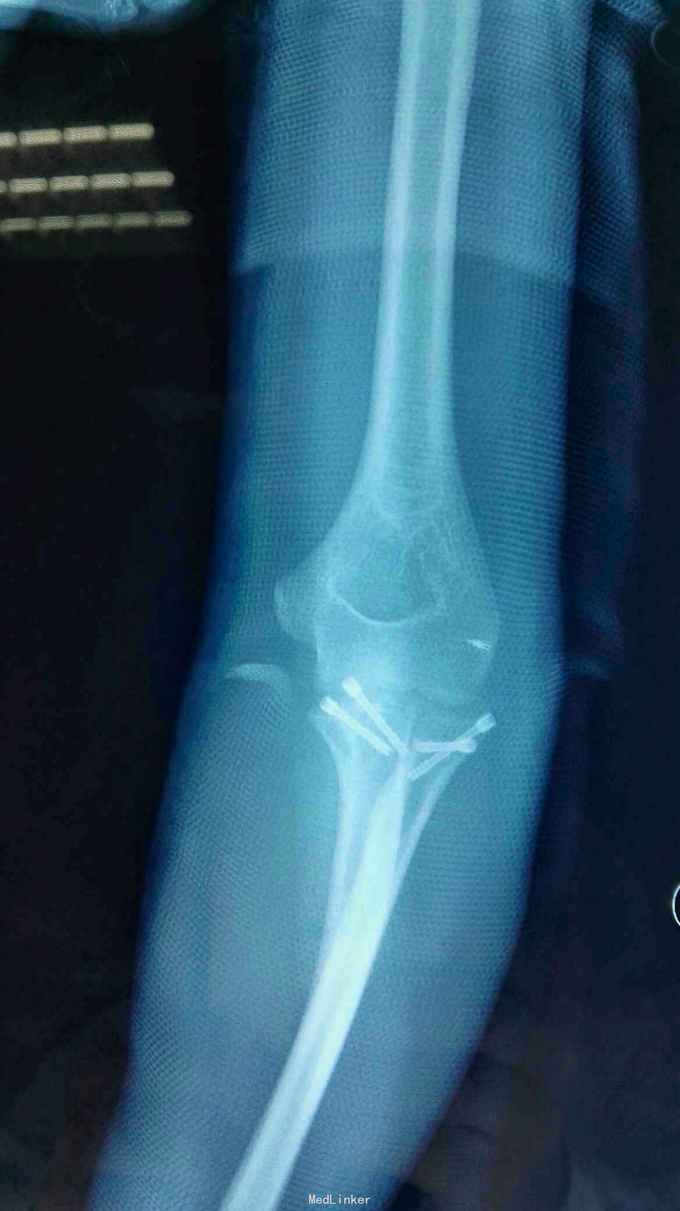

右肘跌伤疼痛伴不能活动1天。 患者,男,14岁,1天前跌倒,感右肘部剧痛,不能活动,急送当地医院拍片示:右肘关节脱位,尺骨冠狀突骨折,右桡骨小头骨折,行手法复位,今来我院就诊。

查体:右肘关节高度肿胀,触痛,活动功能障碍手指末端感觉血运正常。 辅查:x线,CT:右肘关节脱位,右尺骨冠突骨折,右桡骨小头骨折